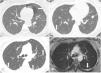

A 34-year-old woman was admitted to our clinic with complaints of exertional dyspnea for 4 years associated with chronic pelvic pain. Since the onset of symptoms, she had three spontaneous pneumothoraces, two in the left lung and one in the right lung that were drained and had complete resolution (Fig. 1A). Bilateral pleurodesis with talc was performed in both the hemithoraces. She had no comorbidities and no history of smoking. She had used chronic combined oral contraceptives. Respiratory examination was normal, and there was no hypoxemia at rest in room air. Chest CT performed one month after the last pneumothorax showed small, regular, and thin-walled cysts in both lungs, without other manifestations such as pleural effusion or pneumothorax (Fig. 1B and C). Pulmonary function tests demonstrated a proportional reduction in FEV1 and FVC (FVC = 44% of predicted), with a moderate reduction in the diffusion capacity of the lungs for carbon monoxide (61% of predicted). Laboratory tests were normal, including negative autoantibodies such as antinuclear antibody, rheumatoid factor, anti-Ro/SSA, and La/SSB. Chest MRI showed slight bilateral posterior pleural thickening with an intermediate signal on T2, that may correspond to the blood content (Fig. 1D). Abdominal and pelvic MRI showed thickening in the uterine retrocervical region with hypersignal on T1 and fat suppression, that may correspond to hemorrhagic areas suggestive of endometriosis. No evidence of renal angiomyolipoma or lymphangioleiomyoma was found. After multidisciplinary discussion, right lung segmentectomy was performed to establish the diagnosis. Histopathological analysis demonstrated endometrioid-type stromal cells around well-represented subpleural cyst that showed evident mural proliferation, with immunohistochemistry negative for melanoma marker antibody (HMB45) and beta-catenin. However, it was positive for Wilm's tumor 1 gene (WT1), CD10, and estrogen receptor, which confirmed the diagnosis of thoracic endometriosis (Fig. 2). CD10 is considered a sensitive immunohistochemical marker for (normal) endometrial stroma and endometrial stromal neoplasms. The WT1 gene has an essential role in the regulation of the development of the urogenital tract. It is expressed both in normal cells of the genital tract (granulosa, myometrium and endometrial stroma) and in tumors of adnexal origin and serous subtype. There was a relationship between spontaneous pneumothorax and the menstrual cycle, with most events occurring in the menstrual phase without any other catamenial manifestations. After a multidisciplinary approach involving a pulmonologist, gynecological surgeon, and thoracic surgeon, treatment with a GnRH analog (goserelin) was started. After treatment for 3 months, the patient was asymptomatic and the cysts remained stable on chest CT.

In (A), axial CT scan demonstrates pulmonary cysts and a pneumothorax (white arrow) during the follicular phase of the menstrual cycle. In (B) and (C), axial reconstructions of CT scans demonstrate small, regular and thin-walled cysts in both lungs (white arrows). In (D), chest MRI shows slight bilateral posterior pleural thickening, with an intermediate signal on T2, that may correspond to blood content (white arrow).

Legend: CT: computed tomography; MRI: magnetic resonance imaging.